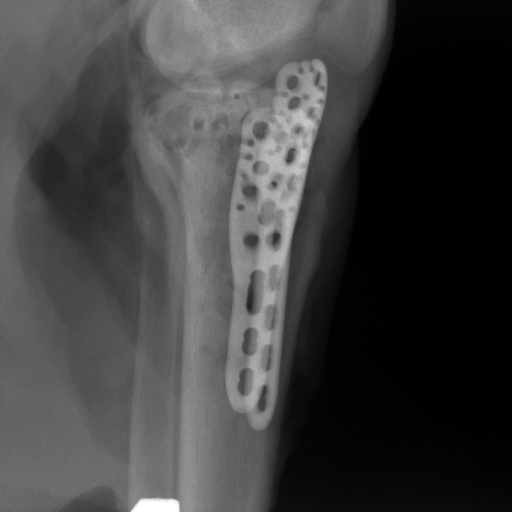

5.4 Real Knee Data with Metal Implants

Refer to caption

Figure 13: Three examples of synthetic perspective projection images for training, intensity window: [0, 4]. The appearance (e.g., image contrast and metal image resolution) of such DRR training images is different from that of real projection images in Fig. 14.

0superscript00^{\circ} perspective

(a) 32.56, 109.85

(b) 18.91, 19.54

180superscript180180^{\circ} perspective

[Uncaptioned image]

(c) 28.11, 112.16

(d) 15.80, 19.27

View difference

0superscript00^{\circ} and 180superscript180180^{\circ} RGB

DRR reference

(e) 29.72, 111.80

(f) 17.14, 19.38

Pix2pixGAN

(g) 29.72, 111.80

(h) 17.50, 19.70

(Fig. 14 continues in the next column.)

TransU-Net

(i) 29.72, 111.80

(j) 16.23, 19.25

Figure 14: The results for the real cadaver leg data. The green dots mark the positions of landmarks in the corresponding reference images. In the first column, the arrows indicate the bone cavity/fracture structures. In the second column, the solid lines mark the widths and heights of the metals. The green ones are measured from the DRR reference, while the red ones are measured in the corresponding perspective projection image. In the last column, the lines mark the centerlines of the metal screws, where the green lines are those from the reference image. The lengths of the lines in mm are displayed in their corresponding subcaptions. Intensity window: [0, 4]. Please zoom in for better visualization.

The complementary view setting for learning perspective deformation is also evaluated on real CBCT projection data. In this evaluation, real CBCT projection data from a dataset of knees with metal implants is used for testing, while DRRs created from volumetric CT datasets with inserted metals is used for training. Three exemplary DRR perspective projection images for training are displayed in Fig. 13, in which synthetic metal implants are inserted [34]. The appearance, e.g., image contrast and metal image resolution, of such DRR training images is different from that of real projection images in Fig. 14. In Fig. 14, the results for three knees, with and without metal implants, are displayed. The first and second rows are the 0superscript00^{\circ} and 180superscript180180^{\circ} perspective projections, respectively, rebinned to the virtual detector with geometric calibration based on their respective principal points and projections of the world origin. The third row displays their difference images, where the magnitude of deviation increases from the center towards the outside like it does in DRRs with an ideal scan trajectory (e.g., Fig. 6(e)), although real projection data suffer from various physical effects like beam hardening and Poisson noise. The fourth row displays the RGB stacks of 0superscript00^{\circ} and 180superscript180180^{\circ} perspective projection images. The magenta and green regions indicate structures with considerable perspective deformation, for example, the knee patella in Fig. 5.4, the top parts of the two metals in Fig. 5.4, and the bottom two screws in Fig. 5.4. The fifth row displays reference images, which are orthogonal projections of iterative reconstruction volumes from measured CBCT projection data. In the reference images, a total of five landmarks are selected, with the positions being marked by the green dots: In Fig. 5.4, two positions at the edges of the knee patella are marked; In Fig. 14(e) and Fig. 14(f), one position at the left edge of the fibula is marked for each image. In addition, a rectangular frame for the two metals is marked by the green dashed lines, while its width and height are indicated by the green solid lines, which are 29.71 mm and 111.99 mm, respectively. In Fig. 14(f), the centerlines of the bottom two screws are sketched by the green lines, which have the lengths of 17.14 mm (middle screw) and 19.38 mm (bottom screw). The corresponding rectangular frame for the two metals and the screw centerlines in the perspective projection images are marked as well, but in red color. In Fig. 14(a), the width and height of the metals are 32.56 mm and 109.85 mm, which have deviations of 2.84 mm and -1.95 mm to the reference ones, respectively. In Fig. 14(b), the centerline lengths are 18.91 mm and 19.54 mm, which have deviations of 1.77 mm and 0.16 mm, respectively. Although the bottom screw has little length deviation to the reference, the orientations of both screws are obviously deviated. The sixth row shows the results of Pix2pixGAN using 0superscript00^{\circ} and 180superscript180180^{\circ} polar inputs. For all of the landmarks, the green reference dots are all located accurately in the Pix2pixGAN images. The rectangular reference frame also accurately covers the metals in Fig. 14(g). In Fig. 14(h), although the two red centerlines do not exactly overlap with the green one, they are very close in lengths and orientations. Please zoom in for better visualization.